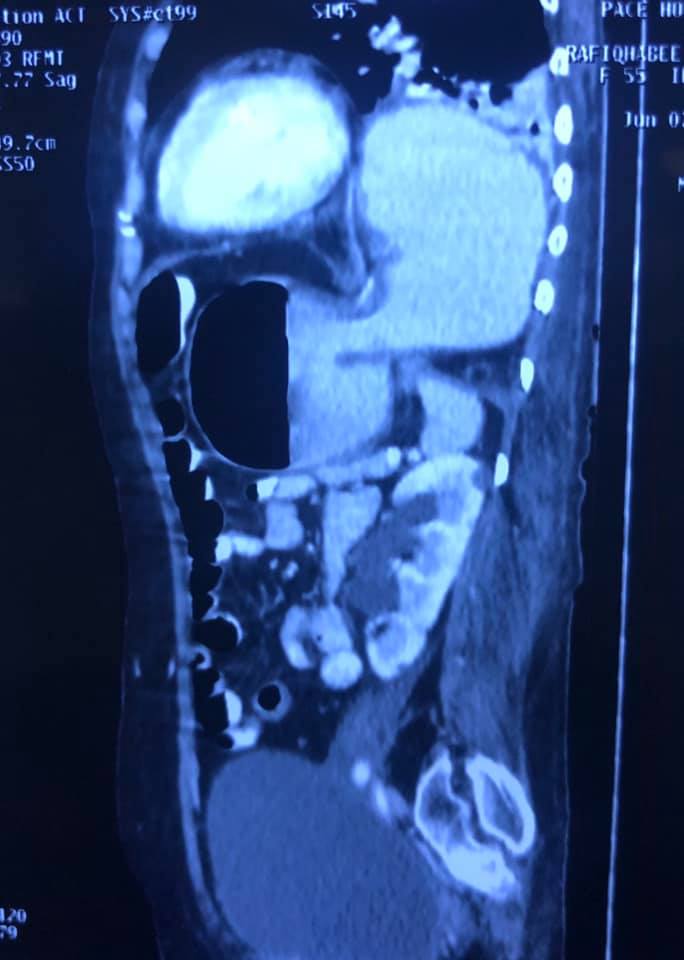

Interesting Images March 2019 : Patient came with an early stage carcinoma rectum, underwent Hemicolectomy surgery then lost to follow-up. Later after 9 month patients presented to us with Stage 4 disease (Carcinoma colon with Liver secondaries). Then we started her on treatment with Chemotherapy along with Monoclonal antibodies with six cycle of above said treatment patient achieved near complete remission. We could achieve very good results with chemotherapy even in patients with Stage 4 disease (Carcinoma colon with Liver secondaries).